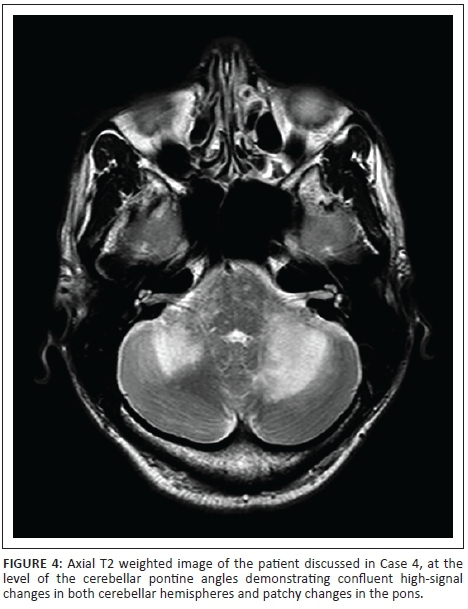

A 38-year-old male patient, HIV-positive with a CD4 count of 143 cells/µL, presented with left hemiparesis, diplopia and ataxia. He was not on HAART. A CT scan of the brain showed asymmetric hypodensities in the cerebellum with no enhancement post contrast. MRI showed bilateral confluent non-enhancing, cerebellar high-signal changes on T2-weighted and FLAIR sequences with patchy changes in the brainstem (Figure 4). The patient was advised regarding antiretroviral therapy (ART) and was discharged.